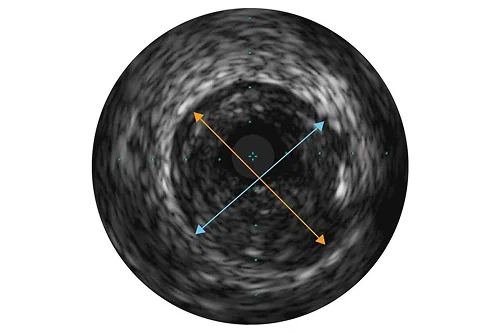

Assessment of vessel size

Vessel diameters may be determined at proximal and distal reference sites by obtaining lumen diameters, mid-wall diameters (halfway between lumen and vessel), or vessel diameters, in order of increasing aggressiveness. If maximum and minimum diameters are used, measurements should bisect the geometric center of the vessel rather than the center of the IVUS catheter.